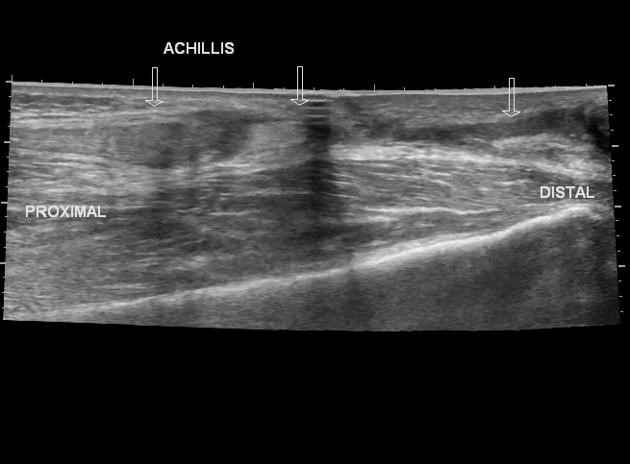

Ultrasound can be used to diagnose a variety of MSK injuries and disorders.

Focused ultrasound imaging has proven to be a useful and cost-efficient tool to many providers when diagnosing and treating their patients. MSK imaging is

primarily used to evaluate traumatic, inflammatory, and degenerative conditions of structures. When superficial imaging is required, ultrasound can

achieve extremely high resolution, quite comparable to that of MRI or CT scanning. It identifies damage or problems in joints, tendons, ligaments, muscles

and nerves where the patient has pain. The ability to provide a dynamic component while evaluating MSK structures gives light to injuries that could otherwise

not be seen.

MSK ultrasound provides dynamic information. Scans can be performed while moving the joint through a range of motion. Ultrasound imaging can help identify:

• Tendinosis/Tendinitis

• Tendon and ligament tears

• Bursitis (inflammation or fluid within the bursa)